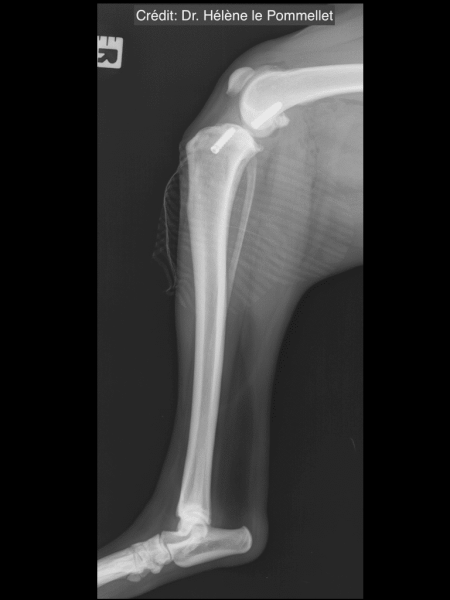

Radiologické snímky